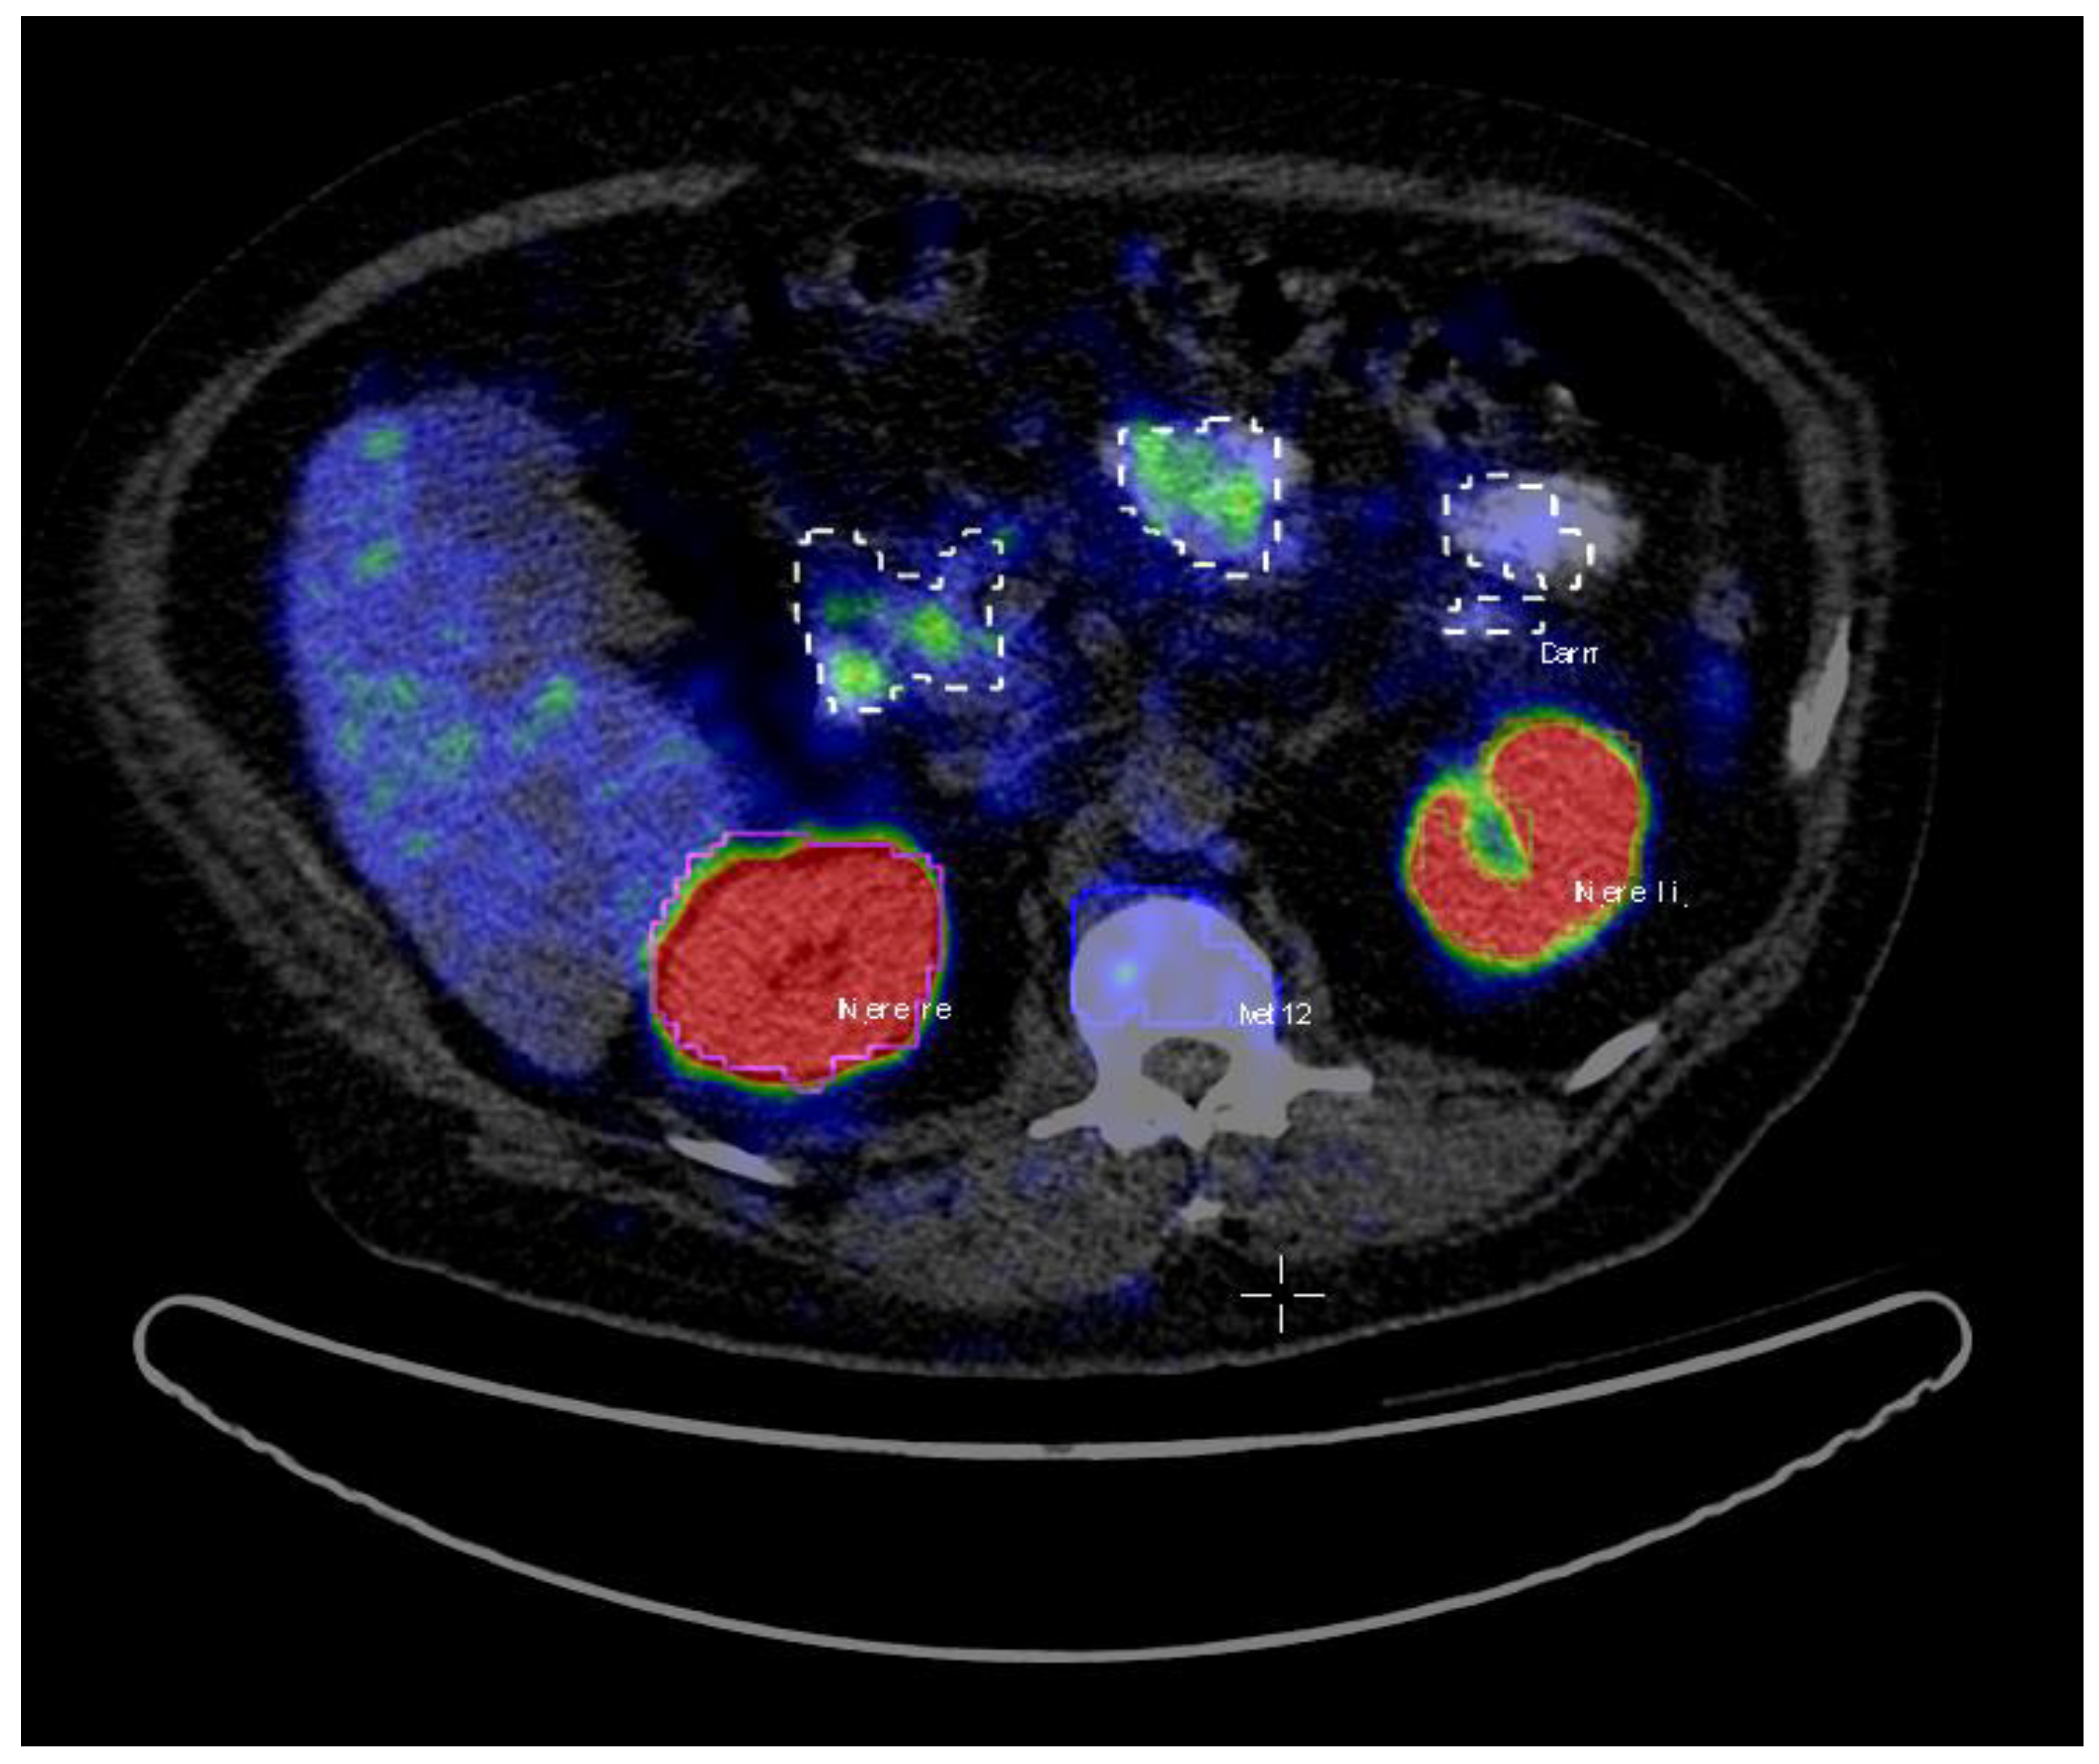

A total of 72 patients were assigned as the training dataset. The patients’ average age was 71 (range: 48–87), and the average Gleason score was 8 (range: 6–10) (Table 1). The PET/CT images data were analyzed using Interview Fusion Software by Mediso Medical Imaging (Budapest, Hungary) [22]. All the hotspots have been identified based on fused PET and CT data. Volumes of interest (VoIs) were manually delineated with a brush tool in the PET images slice by slice (Figure 1). The criteria to choose an uptake was the visible tracer uptake without any predefined threshold. In a second step, the hotspots were classified as pathological or physiological, corresponding to the location they were situated in. The hotspots included primary prostate cancer and metastases in the skeletal system, lymph nodes, as well as physiological uptake in kidneys, liver, glands, gastrointestinal tract (gut) etc. A total number of 2452 hotspots were marked and then categorized as either pathological (total of 1629) or physiological (total of 823).

Figure 1. A sample screenshot from the hotspots’ delineation step using InterView Fusion Software (Mediso, Budapest, Hungary) [22]. The hotspots are identified and delineated slice by slice as 3D volumes of interests (VoIs) by an experienced nuclear medicine physician (the hotspot names translation from German: Niere = kidney, Darm = gut. Moreover, Met stands for metastasis).